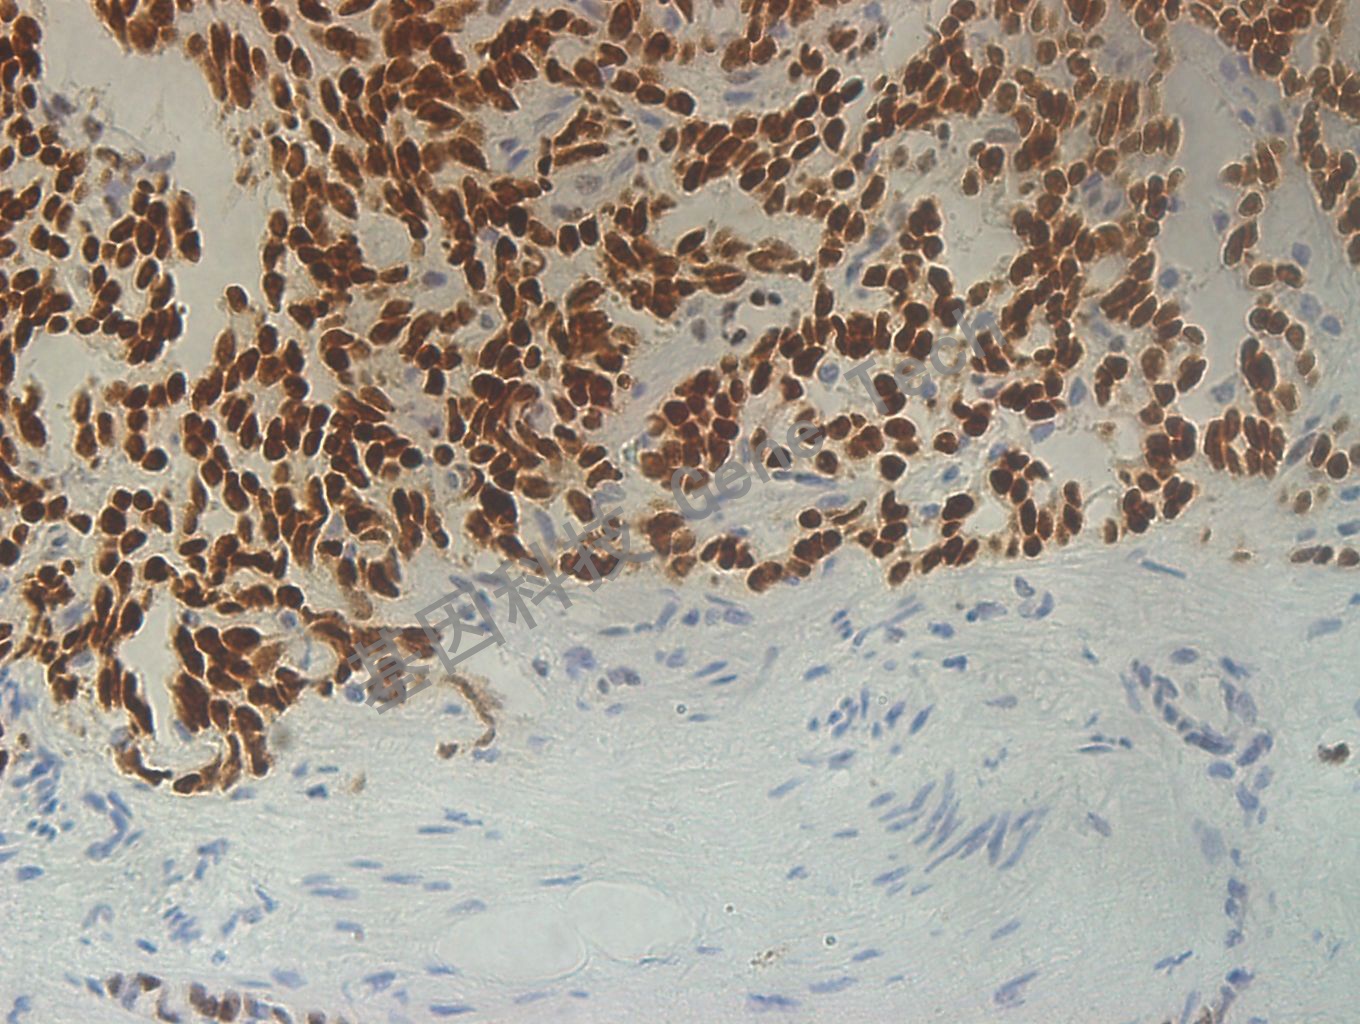

前列腺癌石蜡切片,用 TLE-1(GT2239)染色,细胞核阳性,DAB显色。(40×)